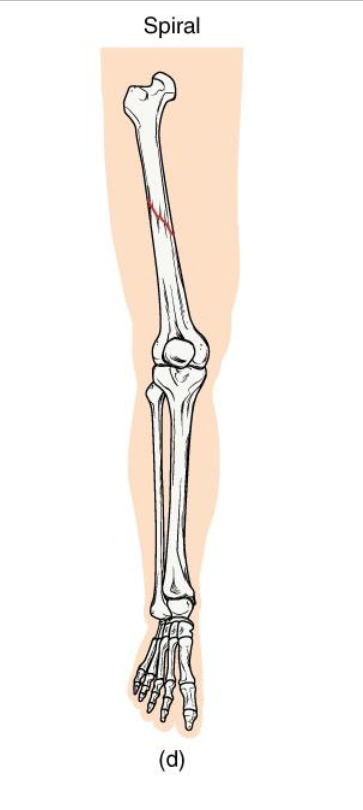

Spiral Fracture

<p><strong>Definition</strong>: Twisting or rotational fracture line around the bone</p><p><strong>Mechanism</strong>: <strong>Rotational force</strong> (ex: skiing, twisting fall, child abuse case)</p><p><strong>Clinical note</strong>: Jagged edges → difficult reduction; may damage surrounding soft tissue.</p><p><strong>Key Concept</strong>: Indicates torque forces; look for rotational injury pattern</p>